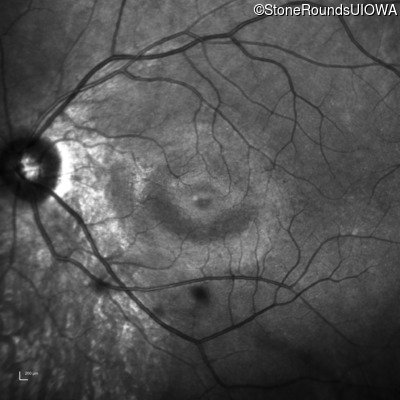

Age at visit: 14 years

OD OS

This fourteen year old female has had poor vision in dim light since at least age 6.